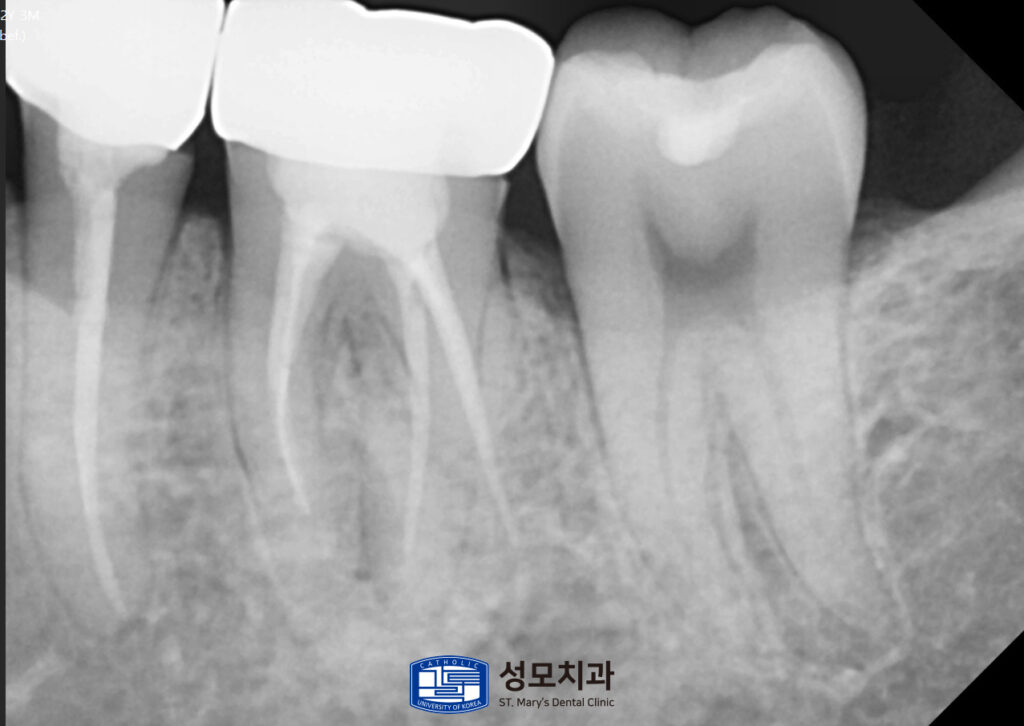

왼쪽 위아래에서는 내부 코어까지만 형성된 상태로

최종 보철이 미완성인 치아 두 개가 확인되었는데요.

코어까지만 형성된 채로 방치되어 있던

두 치아는 남은 치질의 두께를

재평가한 후 최종 크라운을 장착했습니다.

이 과정에서 중심 교합 접촉은 넓고

안정적으로 분산시키고 측방 운동 시

과도한 접촉이 걸리지 않도록

교합지를 이용해 미세 조정을 반복했습니다.

치관의 약 3분의 1만 남았던 치아는

치근 길이, 치주 지지, 치경부

균열 여부를 종합 평가한 결과

보존 치료가 가능하다고 판단했습니다.

근관치료로 감염을 제거하고

코어 빌드업으로 남은 치질을 보강하여

크라운을 안정적으로 지지하게 했습니다.